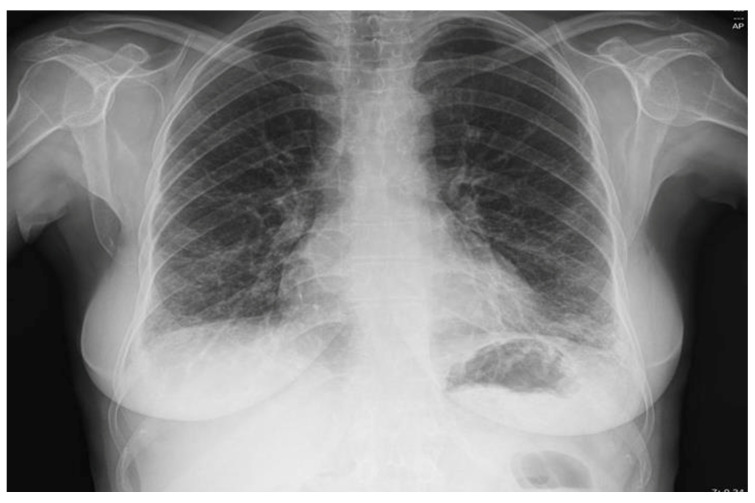

背景和临床意义:抗合成酶综合征(ASyS)是一种罕见的自身免疫性疾病,其特征是存在抗氨基酰基-t核糖核酸(RNA)合成酶自身抗体,通常与间质性肺疾病(ILD)、炎症性肌病和关节炎有关。其他临床特征可能包括雷诺现象和“机械师之手”。在抗合成酶抗体中,抗pl -12与显性或孤立性ILD明显相关,并且可能在没有临床明显肌炎的情况下发生,从而使及时诊断复杂化。病例介绍:我们报告一位45岁的非吸烟女性患者,既往诊断为血清阴性类风湿性关节炎(RA),出现进行性呼吸困难、干咳和恶心症状。高分辨率计算机断层扫描显示非特异性间质性肺炎(NSIP)模式。尽管肌酸激酶和乳酸脱氢酶水平正常,血清学检查显示抗pl -12和抗ro52抗体阳性,支持抗合成酶综合征的诊断,无肌炎,符合conors和Solomon的ASyS诊断标准。皮质类固醇和环磷酰胺治疗可诱导临床和呼吸功能改善,而硫唑嘌呤用于维持。结论:该病例强调了抗合成酶综合征的临床异质性,并强调了在没有肌炎的情况下,抗pl -12相关ILD所带来的诊断挑战。重要的是,该研究表明,在已有风湿病诊断的患者中,非典型肺部表现的出现需要重复血清学评估,以评估ASyS和其他自身免疫性疾病。早期诊断和免疫抑制治疗对优化预后至关重要。

Background and Clinical Significance: Antisynthetase syndrome (ASyS) is a rare autoimmune entity defined by the presence of anti-aminoacyl-t ribonucleic acid (RNA) synthetase autoantibodies and classically associated with a triad of interstitial lung disease (ILD), inflammatory myopathy, and arthritis. Additional clinical features may include Raynaud's phenomenon and "mechanic's hands". Among antisynthetase antibodies, anti-PL-12 is notably associated with predominant or isolated ILD and may occur in the absence of clinically evident myositis, thereby complicating timely diagnosis. Case Presentation: We are presenting a 45-year-old non-smoking female patient with a prior diagnosis of seronegative rheumatoid arthritis (RA) who developed progressive dyspnea, dry cough, and sicca symptoms. High-resolution computed tomography revealed a nonspecific interstitial pneumonia (NSIP) pattern. Despite normal creatine kinase and lactate dehydrogenase levels, serological work-up revealed positive anti-PL-12 and anti-Ro52 antibodies, supporting a diagnosis of antisynthetase syndrome without myositis, fulfilling the diagnostic criteria for ASyS per Connors and Solomon. Treatment with corticosteroids and cyclophosphamide induced clinical and functional respiratory improvement, while azathioprine was initiated for maintenance. Conclusions: This case underscores the clinical heterogeneity of antisynthetase syndrome and highlights the diagnostic challenge posed by anti-PL-12-associated ILD in the absence of myositis. Importantly, it demonstrates that in patients with pre-existing rheumatologic diagnoses, the emergence of atypical pulmonary manifestations warrants repeat serologic evaluation to assess ASyS and other autoimmune conditions. Early diagnosis and immunosuppressive treatment are essential to optimize outcomes.